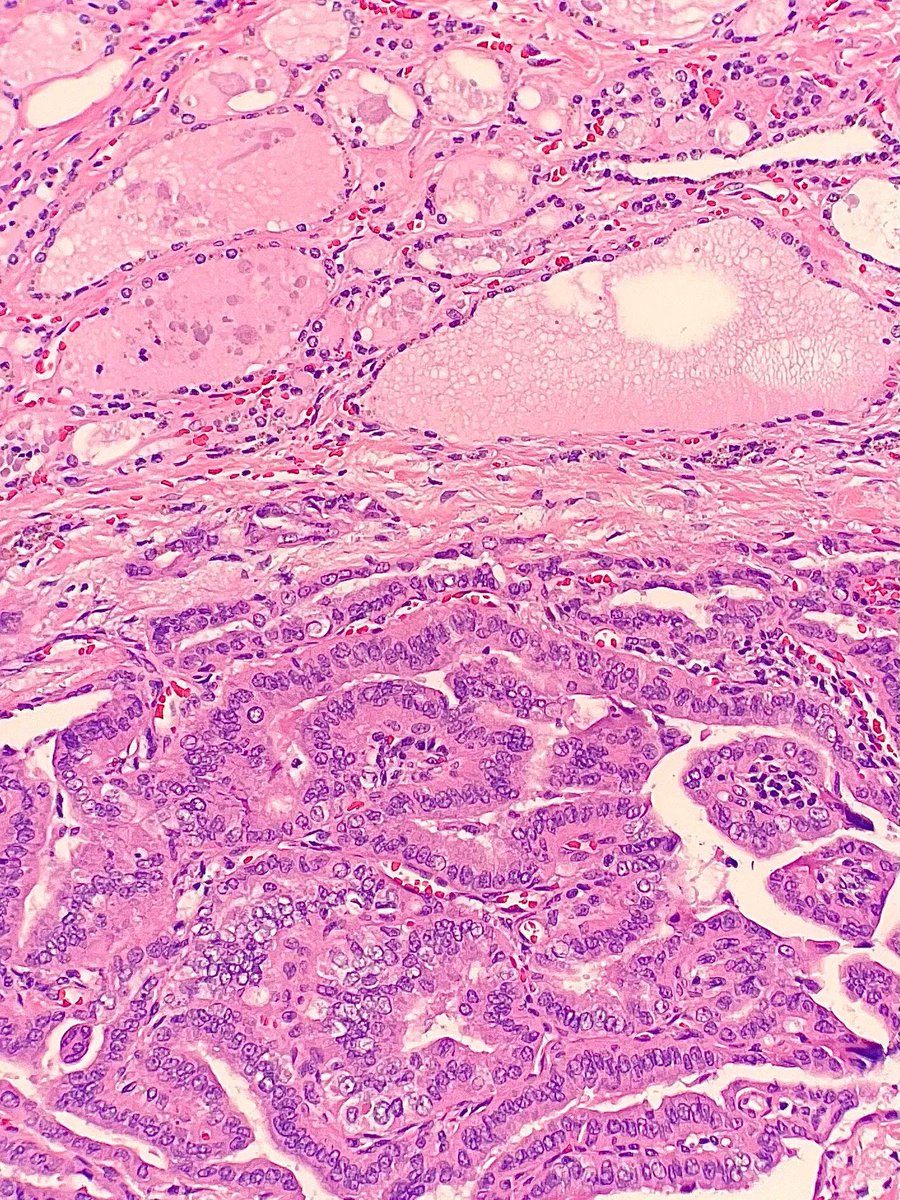

Tumor with an EGFR p.G719A mutation. What type of tumor is shown? Answer: kikoxp.com/posts/18719 #PathTwitter #MolPath #MedTwitter #PathArt